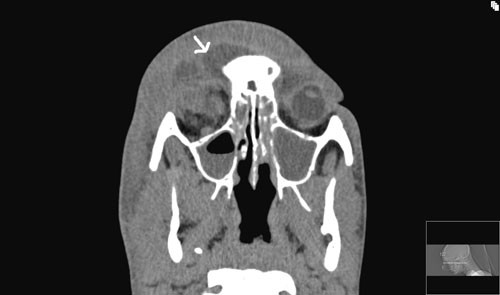

Øre-nese-hals-lege hadde tilsyn fire dager etter innkomst. Han fant økende periorbitalt ødem. Fremre og bakre rhinoskopi viste ikke påfallende sekresjon i nesekaviteten. Det ble funnet oppvekst av betahemolytiske streptokokker som var sensible for penicillin, og gramnegative staver som var sensible for metronidazol i blodkultur. To dager etter oppstart av behandling hadde CRP falt fra 200 til 100, men fire dager etter innkomst var CRP økt til 155. Det ble tatt CT av bihuler uten kontrast som viste pansinusitt og orbital hevelse som presset bulbus oculi utover (fig 1).

Pasienten fikk økende hevelse over øyet og i øyelokket til tross for antibiotikabehandling, og CT viste pansinusitt. Tentativ diagnose var begynnende periorbital abscess. Lokalsykehuset ønsket vurdering av indikasjon for bihulekirurgi og videre antibiotikabehandling. Pasienten ble overflyttet til regionsykehuset for å kunne nytte kompetanse fra avdelinger for øre-nese-hals, øye og eventuelt infeksjonsmedisin.